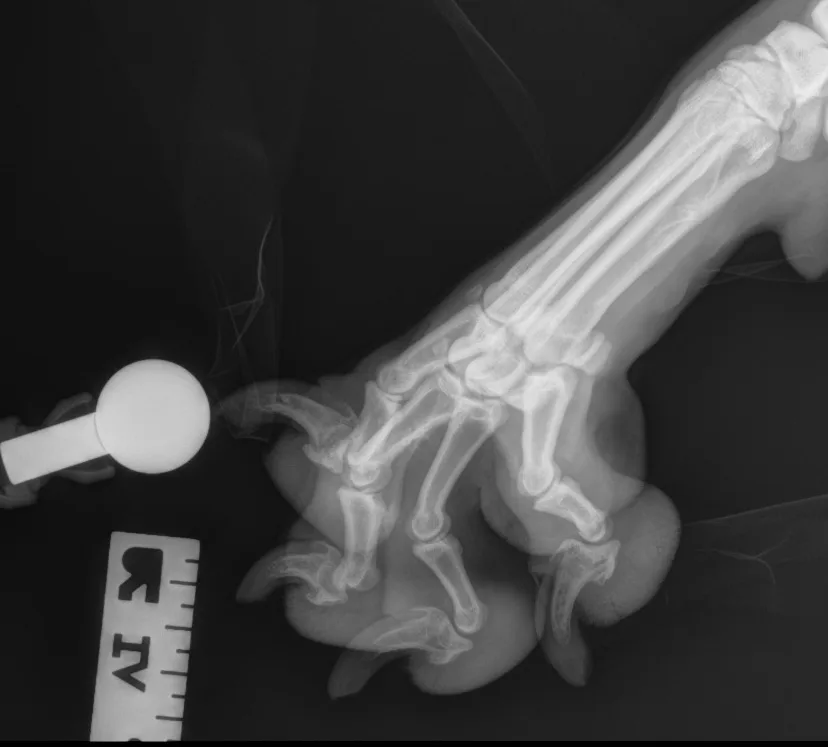

Step-by-Step: Positioning a Pelvic Limb for a Lateral View of the Digits

Place the patient in lateral recumbency with the affected limb on the table. Place a small object (eg, foam pad, gauze) under the calcaneus to keep the limb level and prevent overrotation of the limb and digits. Manually separate and tape down the digits (or use a wooden spoon to press, spread, and tape down the digits) to prevent to prevent superimposition on the radiograph—all digits should be visibly exposed and not overlap. Use a radiographic marker (eg, spherical ball marker, radiopaque numbered marker) to identify the different digits.

Step 2: Position the Beam

Center the collimator beam over the tarsometatarsal joints to include the distal metatarsals and all digits (the tarsus can also be included).

Author Insight

In these examples, the spherical marker ball was placed adjacent to digit V. Radiopaque numbered markers can also be used to individually identify each digit (not shown here). All digits should be separate and identifiable (arrows). The phalanges of each digit should be visible down through the toenail.